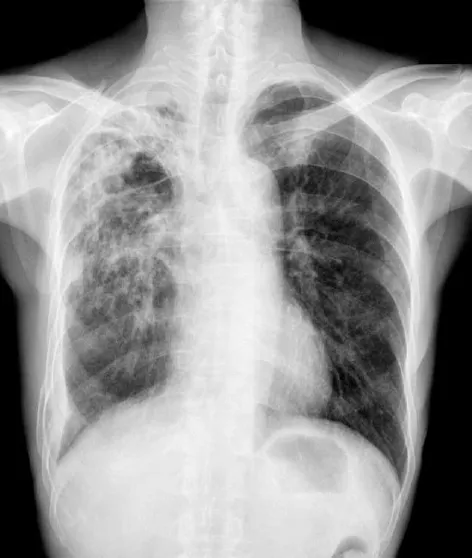

【108-2 醫學(三) 第45題】70歲的男性,因為咳嗽10個月及體重減輕就醫,其胸部X光檢查如附圖。關於進一步的檢驗,下列何者最不適當?